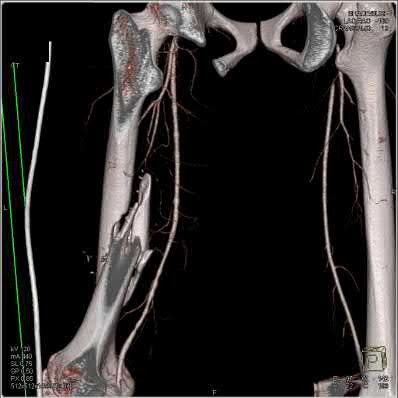

Question 3:

A 15-year-old boy presents with a permeative lytic lesion in the femoral diaphysis with aggressive periosteal reaction ('onion skinning'). Biopsy reveals uniform small round blue cells. Cytogenetic analysis of this tumor will most likely demonstrate which of the following translocations?

Correct Answer: t(11;22)

Explanation:

The clinical and radiographic description is classic for Ewing sarcoma. The characteristic cytogenetic abnormality is a balanced translocation t(11;22)(q24;q12), which fuses the EWS gene on chromosome 22 with the FLI1 gene on chromosome 11. This is seen in approximately 85-90% of Ewing sarcomas. t(9;22) is the Philadelphia chromosome (CML), t(X;18) is seen in synovial sarcoma, t(2;13) in alveolar rhabdomyosarcoma, and t(12;16) in myxoid liposarcoma.